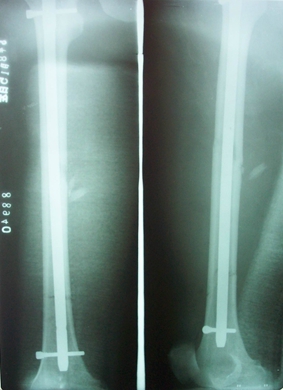

燕化医院开展手术治疗四肢、骨盆骨折患者取得了良好的效果。股骨颈骨折一般以全髋关节置换(THA)和半髋关节置换为主;而对于股骨转子间骨折的外科治疗多采用内固定手术,包括锁定钢板;动力髋系统即DHS、PFN(A)。具有创伤小(微创)、内固定牢固、术后恢复快便于提早下地活动等优点。肱骨、尺桡骨、股骨干、胫骨干的骨折主要采用带锁髓内钉和锁定钢板治疗;复杂的骨盆骨折则采用切开复位,重建钢板治疗。

图5. 股骨干多段骨折

图6. 股骨干多段骨折带锁髓内钉内固定术后